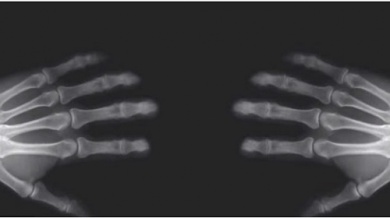

Les articulations sont le point où les os se retrouvent et s’unissent.

Toutes les articulations contiennent une zone appelée capsule articulaire. C’est une zone qui les protège et qui contient un lubrifiant naturel appelé liquide synovial. Ce lubrifiant est nécessaire pour le mouvement des articulations.

C’est précisément ce liquide qui influe sur le fameux “craquement” car il y a de l’air à l’intérieur de celui-ci. Au moment de croiser les jointures, l’articulation se sépare et élargit l’espace de l’intérieur de la capsule articulaire. Ceci entraîne ainsi les gaz dissouts à former des bulles pour occuper le nouvel espace créé.

En exerçant une force sur les jointures, les bulles formées s’échappent rapidement. Cela provoque par conséquent le son caractéristique des craquements.

Après ce craquement, il n’est pas possible de répéter l’action immédiatement. En effet, les articulations doivent d’abord reprendre leur taille normale et les gaz doivent se dissoudre dans le liquide.